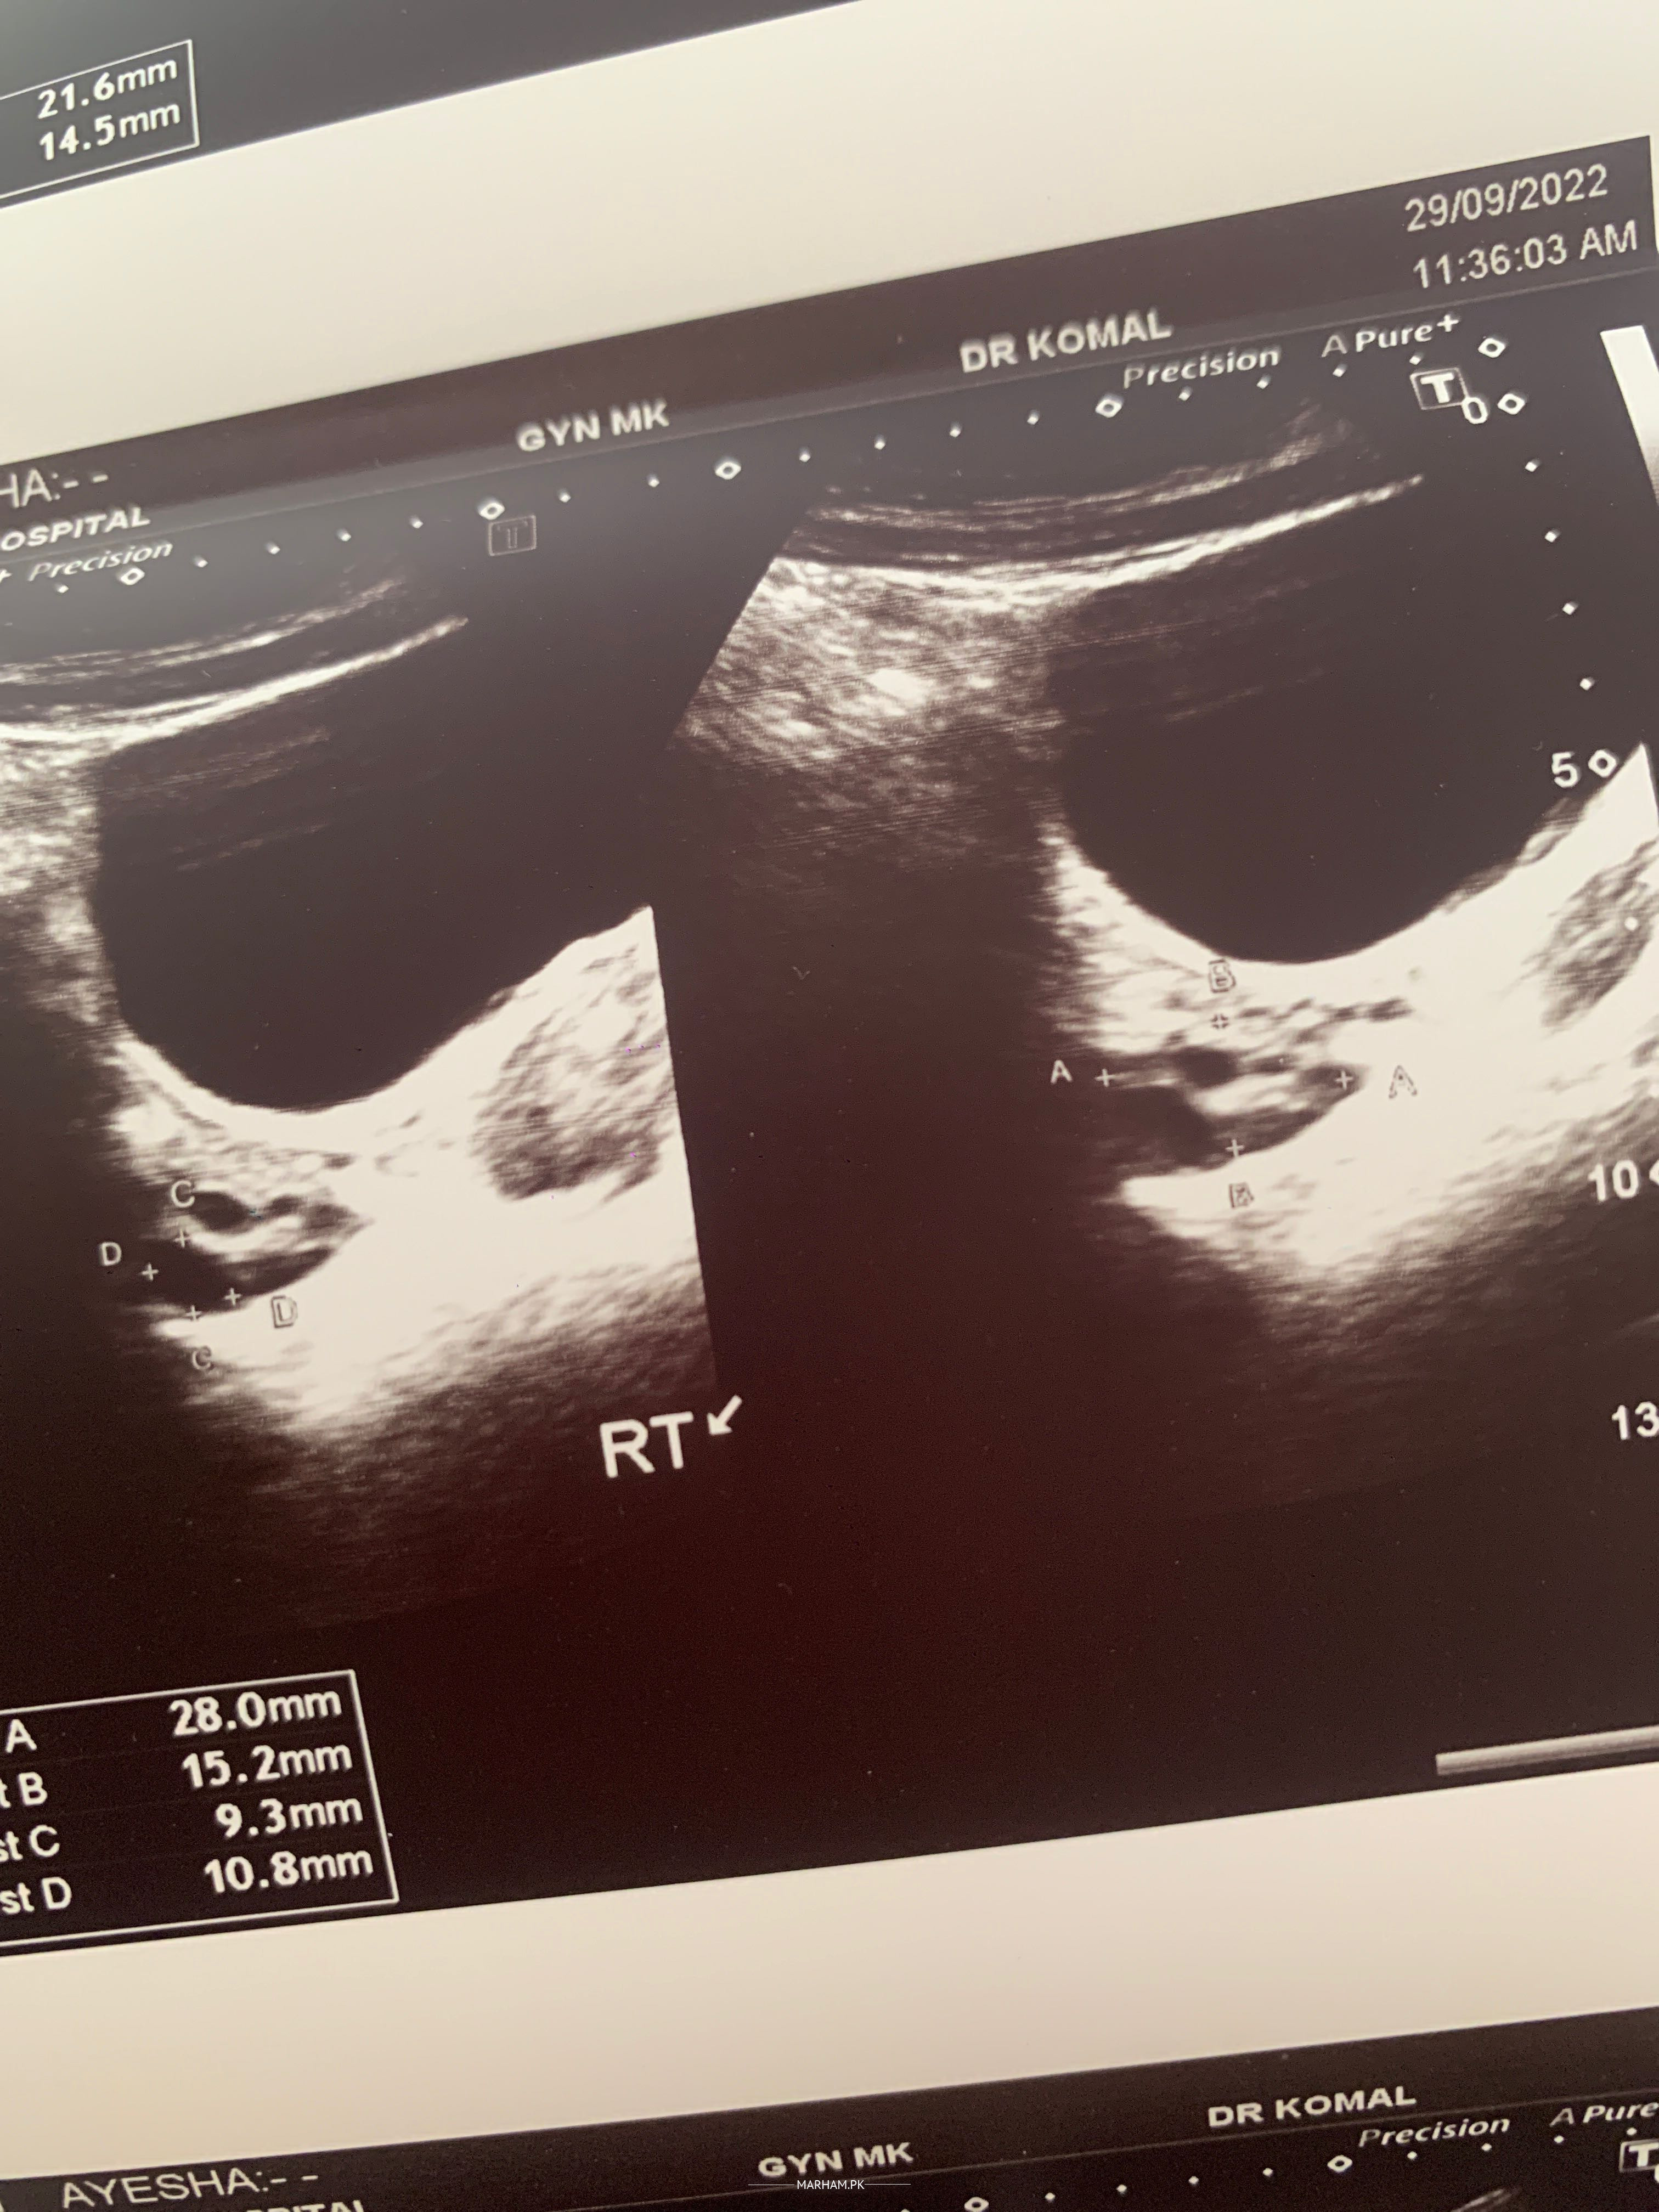

Kindly check my report and reply I’m in tension why is issue? Thankyou

Attach Photo here: